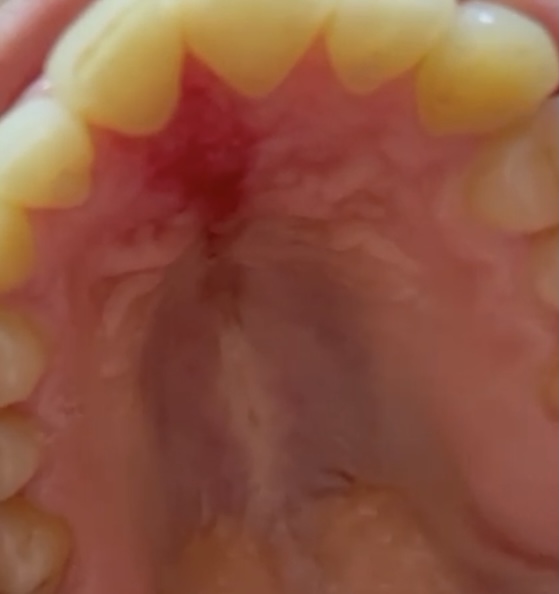

Rigonfiamento palato duro

Buonasera dottori, Sono una ragazza di 26 anni. Martedì 22/06/2021 si è manifestato, in corrispondenza del palato duro, precisamente a partire dall'area dietro gli incisivi, un rigonfiamento ( foto1) che, immaginandolo come se fosse un piccolo germoglio, ha iniziato in poche ore a diramarsi verso tutta l'area del palato duro (mia impressione) fino ad arrestare la sua corsa prima dell'inizio del palato molle. Il giorno successivo quel rigonfiamento doloroso, è diventato una lesione (foto 2) che al terzo giorno, con l'insorgenza della febbre a 37.8, mal di testa, zona ardente intorno alla bocca e dolore alla gola (gola rossa ma assenza di placche o tonsille gonfie) praticamente con una sensazione di infezione dappertutto, ha iniziato a creare uno scavo dietro gli incisivi come se stesse mangiando lembi di pelle. Ho contattato la mia dottoressa che mi ha prescritto cefixoral come antibiotico da assumere in concomitanza ai fermenti lattici, ma con codesto antibiotico i decimi di febbre nei seguenti 3 giorni, fino ala giornata di domenica 27, persistevano e la zona intorno alla bocca era sempre molto calda, però non avevo mal di testa. Il 27 stesso allora ho deciso di recarmi in pronto soccorso per farmi controllare, mi hanno detto di cambiare antibiotico con Amoxicillina+ac clavulanico 1gr ogni 8 ore per 7 giorni, di fare sciacqui con collutorio a base di clorexidina dopo ogni pasto, dieta morbido tiepida e controllo ORL a termine terapia , che ho prenotato quindi per il 5/07/2021; i risultati dell'antibiotico che ho sostituito sono stati molto soddisfacenti perché la lesione (foto 4) sta progressivamente migliorando, e la febbre non è più insorta, tranne ieri sera che si aggirava sempre intorno ai 37.2, complice forse il caldo di questi giorni. Ad ogni modo l'obiettività dell'ORL del pronto soccorso è stata la seguente: cavo orale: era e eritematosa flogistica a livello del terzo anteriore del palato duro(dietro gli incisivi) non fluttuante di circa 0,5mm. Motilità velate e linguale conservata, non medilaizzazione dei pilastri tonsillari. Collo libero. Nell'estate del 2017 si è manifestato un episodio di tonsillite ulcero-necrotica destra(un ORL credeva che si trattasse di un ascesso intratonsillare) che mi stava mangiato letteralmente la tonsilla destra, al momento non ricordo più come son stata curata , sicuramente non con un antibiotico, credo che si trattasse di cortisone. Oltre a questo soffro spesso di tonsilliti croniche, molto spesso di afte ulcerose alla bocca dappertutto (ultimamente anche sulle tonsille stesse), herpes labiale ecc..ma negli ultimi anni senza insorgenza di febbre, quindi il caso per il quale vi ho scritto è stato il primo caso di febbre per infezione dopo tanto tempo. Arrivati a questo punto, sperando di non avervi omesso nulla, volevo chiedervi a titolo informativo di cosa secondo voi possa trattarsi, se quella mia è comunque una condizione che andrebbe studiata meglio o se possa essere legata anche ad un fattore di forte stress, poiché il giorno prima di questa infezione ho avuto a che fare un esame universitario molto pesante. Grazie per l'attenzione!

Per me è tanto difficile dare un parere.. Le gengive dietro gli incisivi spesso vengono traumatizzate se c'è morso profondo (dalle foto non si può vedere perchè manca una foto con i denti in chiusura): Il morso profondo fa si che il cibo o addirittura i denti stessi impattino con la gengiva di quella zona retroincisale. Però che si arrivi ad un quadro sintomatologico così imponente con tanto gonfiore anche più dietro, febbre etc, mi sembra strano. Rimanendo sempre ai denti, se c'è qualche dente devitalizzato (impossibile vederlo dalle foto) od anche qualche frontale che ha avuto un trauma anche tantissimi anni prima (gli incisivi spuntano a 6-7 anni già) si potrebbe essere sviluppata una infezione di questi elementi. Cioè per assurdo, può capitare che il trauma si verifica ad esempio a 8 anni, e che la infezione si sviluppa tantissimi anni dopo.. Però la sede non fa pensare a questo. Sicuramente una visita e rx del dentista può escludere quanto detto finora. L'altro capitolo cui pensare è quello delle stomatiti. Che possono essere di tante varietà differenti. Es. Herpes, mega-afte, micosi,e altre, numerose. Lei ne soffre (e quindi va anche indagato il capitolo della salute generale con analisi varie). Buona la scelta dell'otorino, che in ospedale può fare anche prelievi ed analisi per vedere se si scopre qualche germe. Il dentista vedrà bene i denti (e la placca) ma normalmente non è attrezzato per cercare i germi con i prelievi e le analisi ospedaliere. Se dovessi andare per intuito, oltre a rassicurarla che non mi sembra particolarmente allarmante, penserei ad una afta megasiderale. Ma la probabilità che io abbia ragione non è molto alta..Lo dico solo per rassicurarla fino al giorno 5.